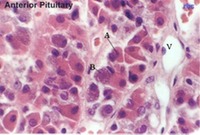

Mammary Glands